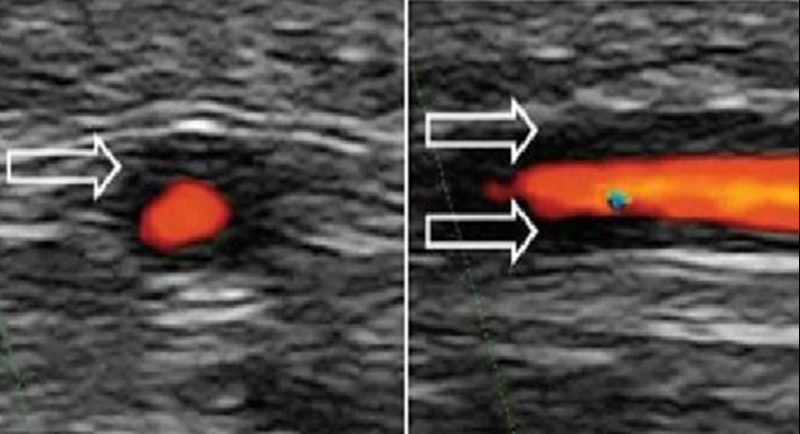

手順は医師の診療内容や患者の健康状態によって異なる場合があります。医師によっては、超音波やインターベンショナルラジオロジーなどの医療画像をガイダンスとして使用して腰椎穿刺を行う場合があります。